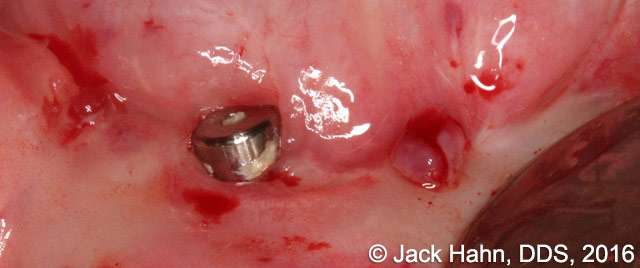

CASE #9 Removal of Failed Dental Implant

Jack Hahn, DDS, removed a failed Bicon implant. The labial plate was absent and the surrounding soft tissue was inflamed and suppurating. All remnants of soft and fibrotic tissue were removed using a LightScalpel CO2 laser. The site was then grafted with Newport Biologics mineralized cancellous cortical particular material and covered with Newport Biologics putty. After 6 months of healing and new bone formation, Dr. Hahn will place a new implant in #8 area.